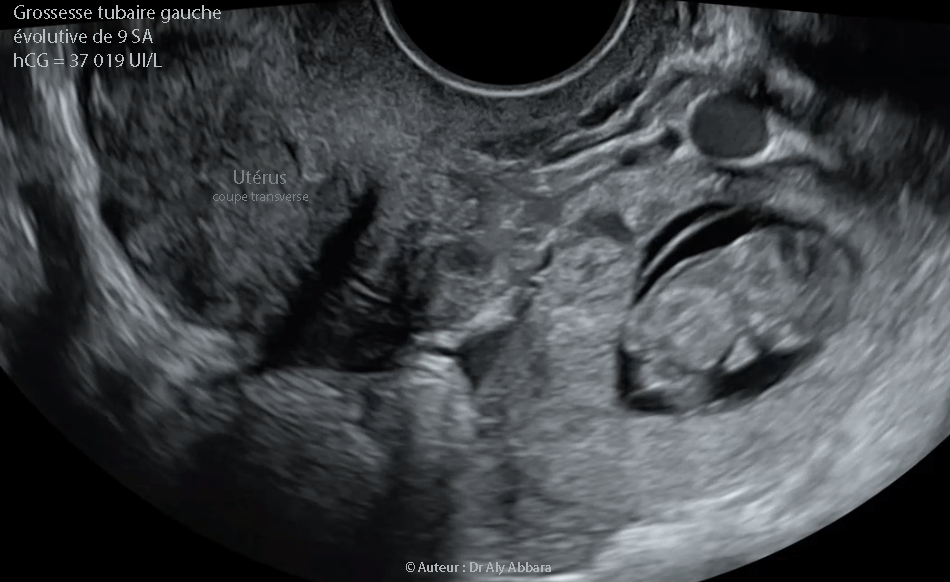

Grossesse extra-utérine tubaire distale évolutive âgée de 9 SA et 2 jours : activité cardiaque positive ; mouvements actifs positifs ; longueur craniocaudale égale à 26,4 mm - coupe transverse de l'utérus

• Images cliniques peropératoires et une séquences vidéos (type *.MP4 et GIF animé) d'une exploration échographique par voie transvaginale (coupe transverse de l'utérus) mettant en évidence la présence d'une grossesse extra-utérine évolutive de la portion moyenne de la trompe utérine gauche et âgée de 9 SA et 1 jours :

• Sur d'autres coupes, on observe la présence d'une petite lame d'épanchement intra-péritonéal située exclusivement dans le cul-de-sac de Douglas.

• Cette grossesse ectopique tubaire gauche évolutive est associée à un tableau clinique comportant un retard de règles d'une durée indéterminable par la patiente avec des métrorragies depuis quelques jours, mais aucune douleur spontanée ou provoquée lors l'examen clinique et échographique.

• Biologie : le dosage de β-hCG plasmatique était égal à 37 019 UI/l.